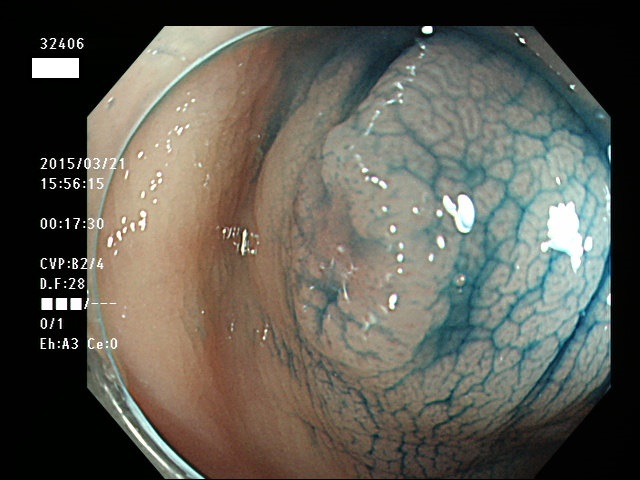

上記100名より抽出した平坦・陥凹型腺腫(=癌化の危険が高いが見落としやすい病変)の内視鏡写真